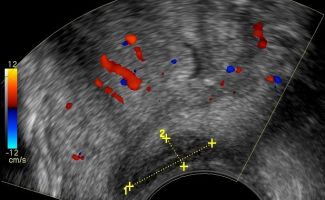

- Peripheral Prostate Zone: The exam can detect focal lesions, such as neoplasms, in the peripheral zone of the prostate.

- Central Prostate Zone: The central zone can be checked for the presence of inflammation, abscesses, calcifications, or other space-occupying lesions.

The Transrectal Ultrasound provides more information about the size, morphology, and focal lesions of the prostate compared to the lower abdominal ultrasound. As a specialized examination, it is performed when there are clinical and biochemical indications, such as elevated PSA (prostate-specific antigen).